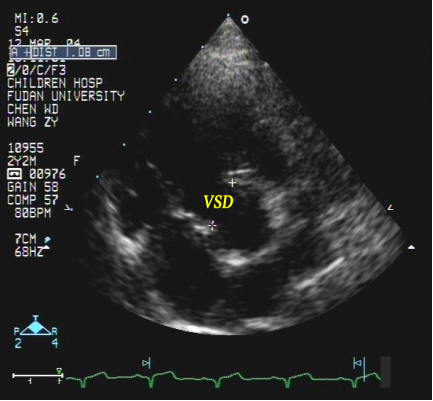

室间隔缺损:超声心动图表现

室间隔缺损(流出道部)